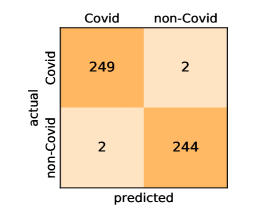

Here, we present and discuss the obtained results for detecting COVID-19 on the considered CT image datasets with different deep networks. We report the quantitative results along with the confusion matrices for every single architecture of the adopted networks.

On the SARS-CoV-2 CT dataset, ResNet101 achieves the best overall performance with respect to almost all evaluation metrics, with an average accuracy and F1-score of and , respectively. The model also achieves an average sensitivity rate of indicating that, on average, only two COVID-19 images are falsely predicted as negatives. It is also powerful enough to correctly identify all Non-COVID-19 cases with only one false positive resulting a specificity rate of . The highest sensitivity score of is achieved by the InceptionV3 model, where only one COVID-19 image is falsely predicted as negative on average. The SqueezeNet model obtains the lowest performance with respect to all evaluation metrics with a fairly acceptable average accuracy and sensitivity scores of and , respectively. Also the ShuffleNet architecture obtains satisfactory performance with approximately improvements on average for all metrics compared with SqueezeNet. Although the results obtained by these models are inferior compared with the rest of models, but they are more efficient. This matches their main objective of reducing the computational costs rather than improving their visual recognition abilities. The rest of models achieve competitive performance and very promising results with slight performance differences. Comparing the different variants of ResNet and DenseNet, we can see that the deeper variants from each architecture yield a slightly better performance. The deeper ResNet101 and ResNeXt101 show a marginal gain in performance compared with their shallower counterparts. The details about class-wise results for each model are summarized in the confusion matrices in Figure 9.

It is worthy mentioning that on the SARS-CoV-2 CT dataset the inter-fold variations are minimal and usually below one percent, showing the robustness of our fine-tuning strategy. For some of the architectures like the DenseNet variants we observe a larger confidence interval than their actual differences in recognition performance. This means that the DenseNets and the deeper ResNet variants share a very similar performance and are almost indistinguishable from each other. Overall, the obtained results by our models are better than the recently published ones even when using the same network architectures. We attribute this to the better optimization and transferability of the learned features when applying our fine-tuning strategy.